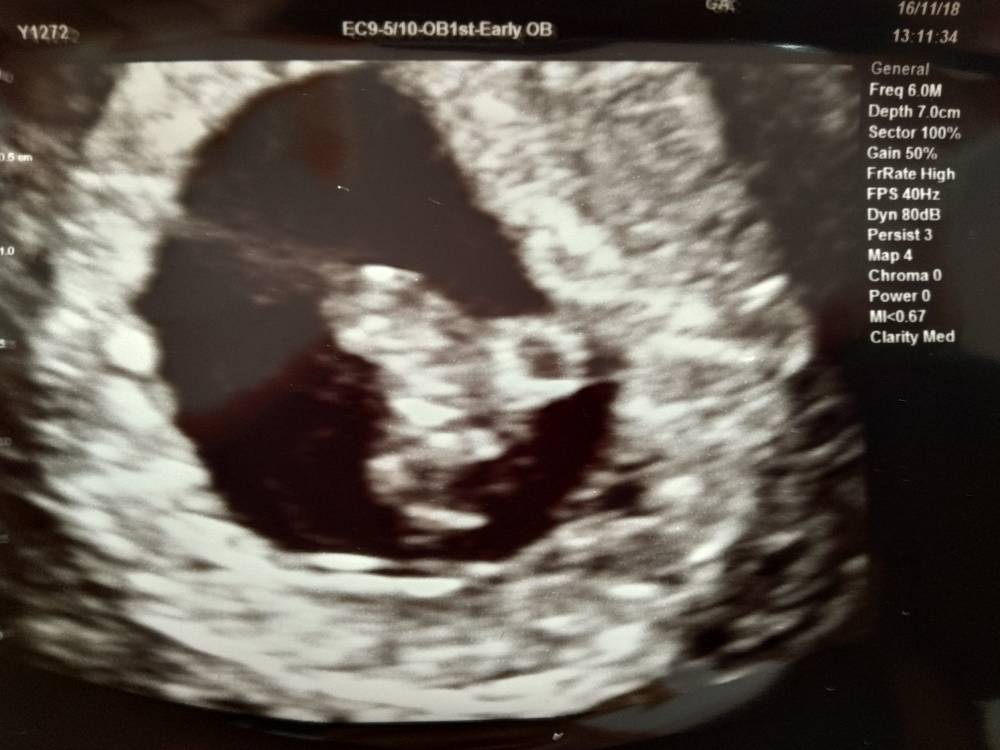

Hej dziewczyny [emoji6] mam nadzieję, że jeszcze mnie tu pamiętacie [emoji3526] chciałam się troszkę pochwalić i podziękować za dotychczasowe wsparcie, bo żadne z moich pytań nie pozostało bez odpowiedzi [emoji3526] bardzo dziękuję!

Jak widać wasze wsparcie i wiara zaoowocowało zdrową ciążą [emoji4]

Dziś byłam na pierwszej wizycie, wg OM 8+0 wg USG 7+5, a więc ciąża dwa dni młodsza.

Mały łobuz ma 14,38mm - gigant! A serduszko bije jak dzwoń (150/m) [emoji3526]

Wszystko generalnie super! A kolejna wizyta 21 grudnia [emoji6]

Życzę wszystkim staraczkom tak cudnego widoku! Pozdrawiam!Zobacz załącznik 917108